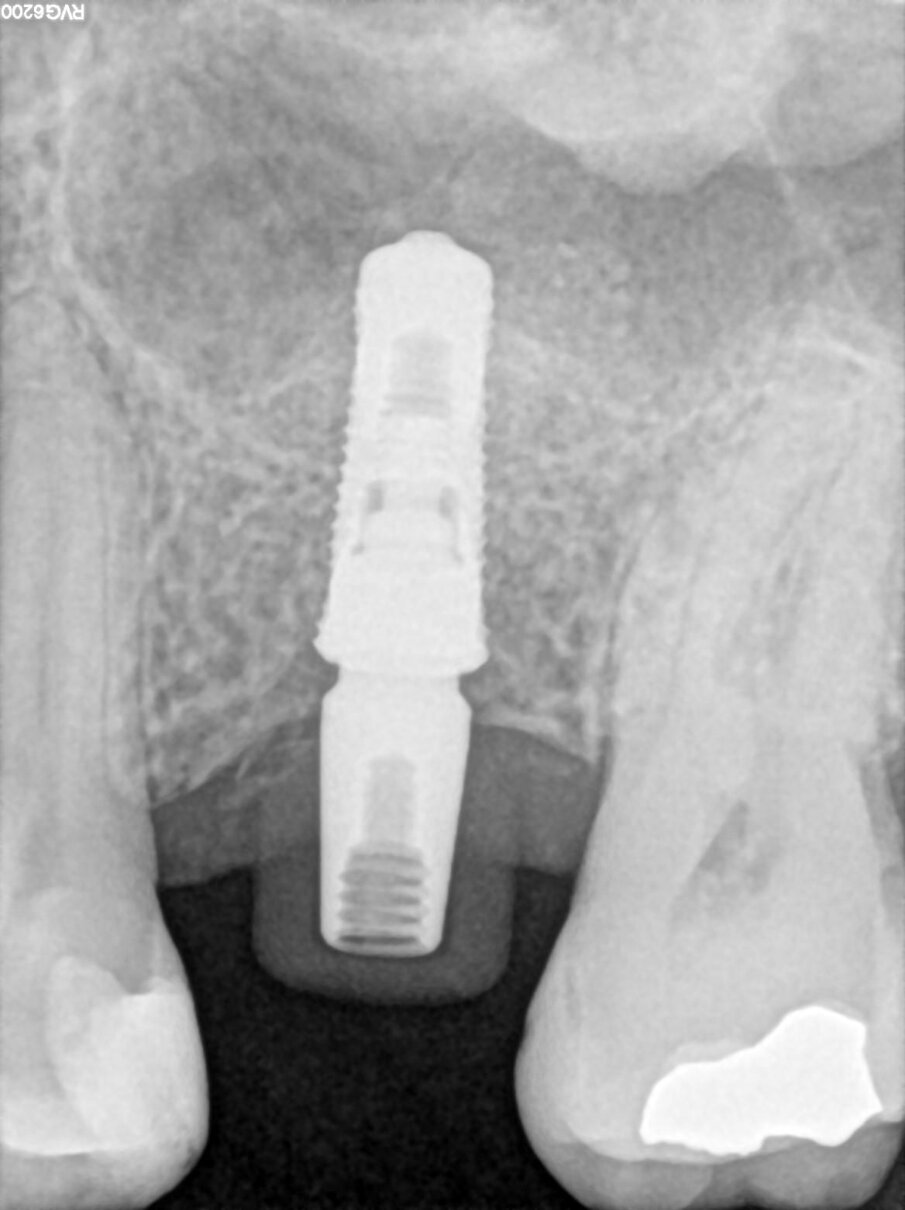

Le radiografie a tre mesi hanno evidenziato un buon rimaneggiamento del biomateriale e segni di neoformazione ossea dal pavimento del seno, confermando le proprietà osteogeniche di OsteoBiol Putty. A sei mesi, l’osso innestato risultava completamente rigenerato, permettendo la finalizzazione protesica con una corona in disilicato di litio cementata su cappa in titanio (Figg. 6-13).

Fig. 7_Follow-up radiografico a 3 mesi.

Fig. 8_Guarigione dopo 4 mesi.